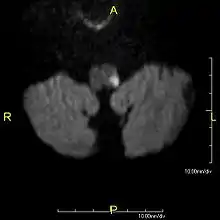

- MRI of Lateral Medullary Infarction (Wallenberg) MedPix Images